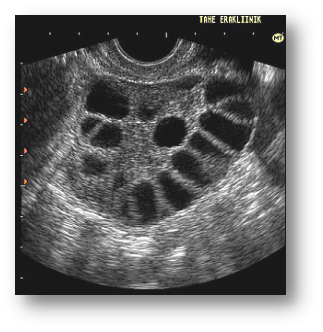

多囊卵巢综合征

◇ 双侧卵巢:卵巢内出现直径为2~9mm的卵泡;卵泡数量多于l2个;和或卵巢容积增大>10mL

◇ 检查:LH高,FSH低,LH/FSH>3, T高